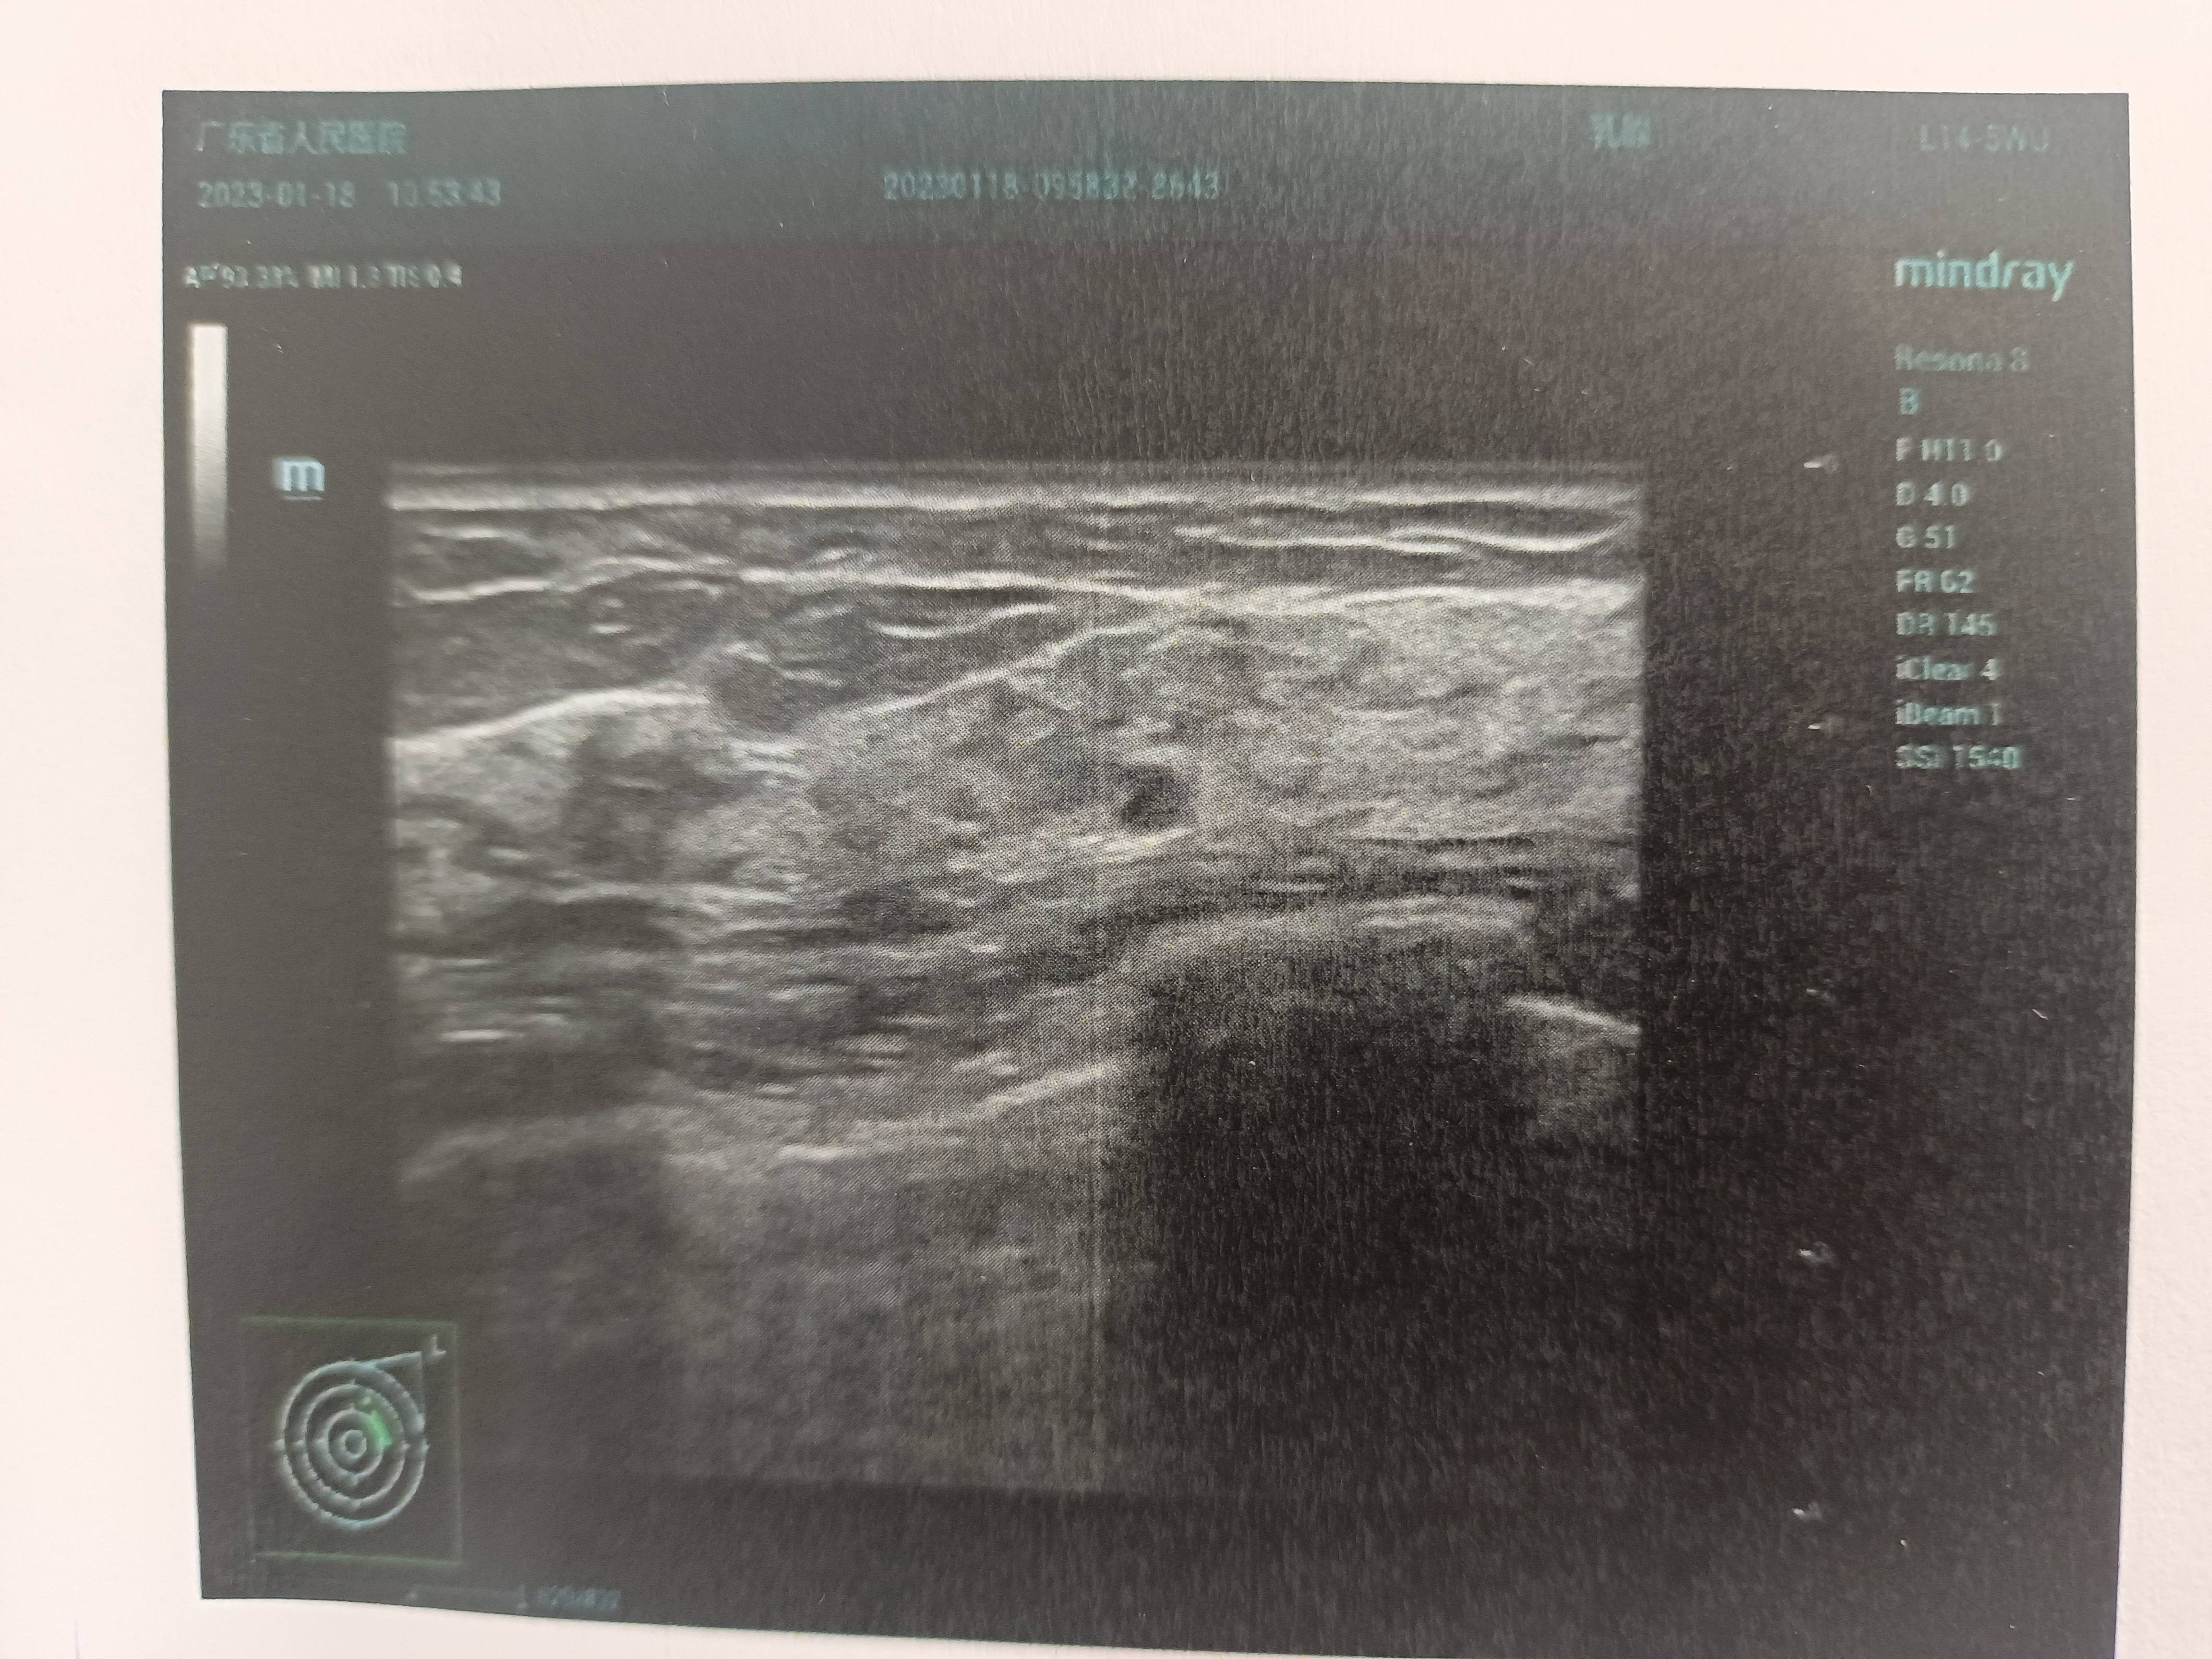

妈妈导管内癌微浸润术后四个月复查,出现淋巴结回声,不知道这个情况考不考虑转移吗?之前在术前和术后三个月内的检查,淋巴结都提示未见异常。有点慌,不知道亲们有没有这种情况?该怎么办?